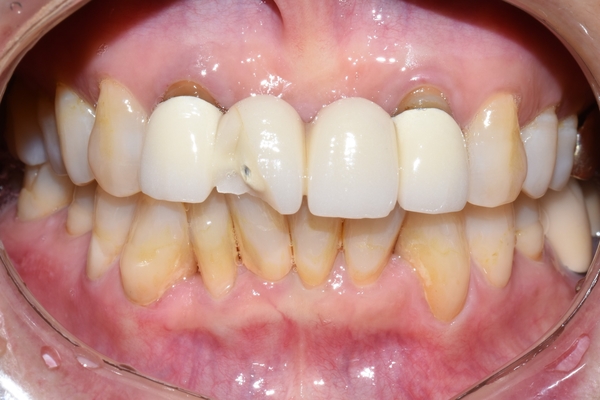

저희 치과를 3년 정도 다니신 환자분의 케이스입니다.

[환자분께서 사진 공개에 동의하셨습니다.]

몇 십년 전에 다른 치과에서 하신 앞니 브릿지가 파절되었다고 내원하셨습니다.

이 몇 십년동안 쓰신 브릿지는 위 엑스레이 처럼

중간 치아 2개는 발치하고 양 옆 치아를 걸어 브릿지를 만든 것입니다.

재료는 PFM으로

깨진 부위는 금속위에 도자기를 올린 부위로 도자기가 충격에 의해 깨져나간 것입니다.

환자분과 상담후, 오래된 브릿지고 몇 십년전 잇몸에 맞춘 상태였기 때문에 잇몸이 내려가면서 브릿지에 싸여있어야 할 치아도 노출 되어 있었기 때문에 브릿지를 새로 제작하기로 하였습니다.